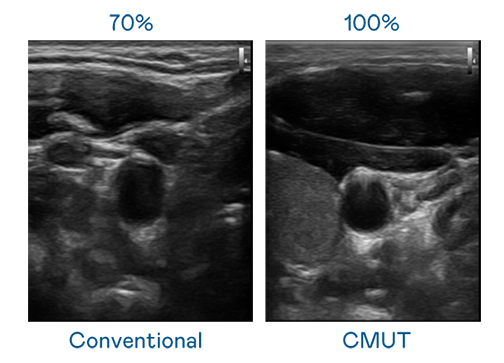

CMUT 技术是一种用电容式微机电元件来产生超音波讯号的技术。与传统 PZT 压电式技术相比,CMUT 频宽增加 30%,更宽频的超音波讯号让影像解析度大幅提升,是实现高影像品质医疗超音波扫描、促进精准医疗发展的关键技术。

大频宽带来超清晰影像

超音波影像的解析度高低,首先取决于探头能发出的讯号频宽。ror体育 CMUT 可提供高清晰的超音波讯号,提供高频宽、高灵敏度、影像纹理细节更高的超音波影像,协助医护人员缩短影像判读时间及利用精准的医疗影像进行诊断。